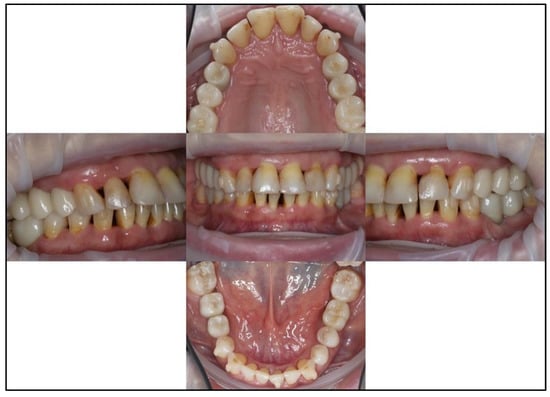

3.1. Case No. 1

3.2. Case No. 2